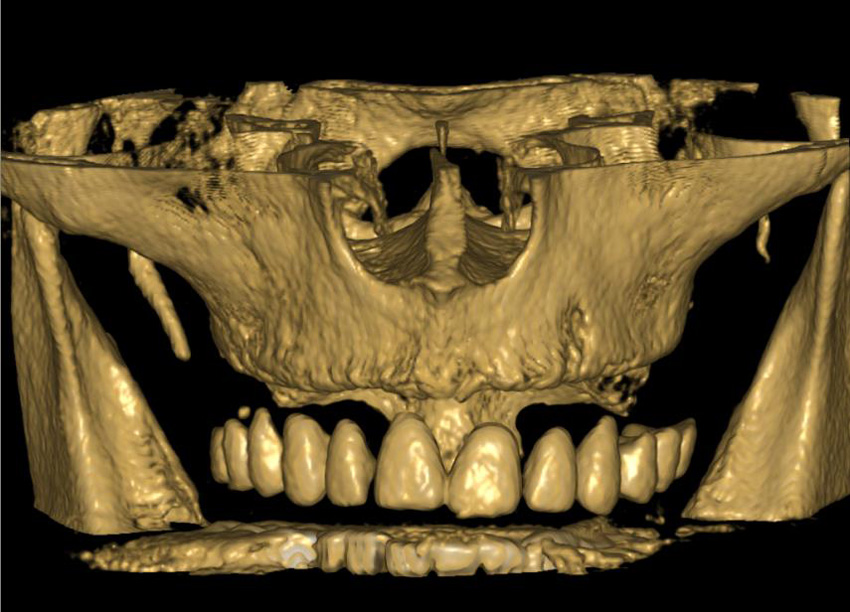

Lékař si vytvoří všechny typy zobrazení potřebných pro naplánování – tedy 2D snímky (panoramatický), příčné řezy i 3D model.

Vidí zde i důležité anatomické útvary – čelistní dutinu, průběh nervu atd. Po proměření množství kosti – šířky i výšky vybere z databáze vhodný typ implantátu a umístí ho do požadované lokality. Ihned vidí jeho pozici ve všech 3 rovinách a na všech snímcích i 3D modelu. Může upravovat podle potřeby jeho pozici, sklon atd.

2) CB CT scan s modelem náhrady

2) CB CT scan pacienta, scan modelu